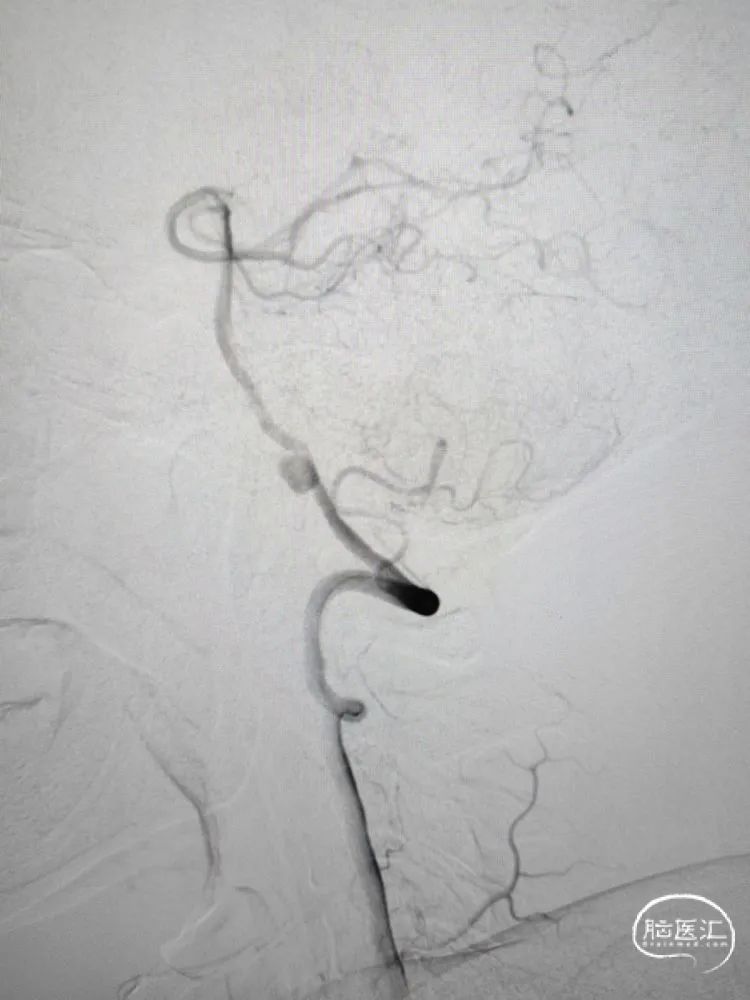

术前影像学检查:全脑血管造影检查提示右侧椎动脉V5段(颅内段)夹层动脉瘤。

动脉瘤大小约5.45mm×7.31mm,动脉瘤远端椎动脉汇合前管径约2.77mm,动脉瘤近端V4段管径约3.80mm,V5段全长约35mm,对侧椎动脉正常。

侧位造影